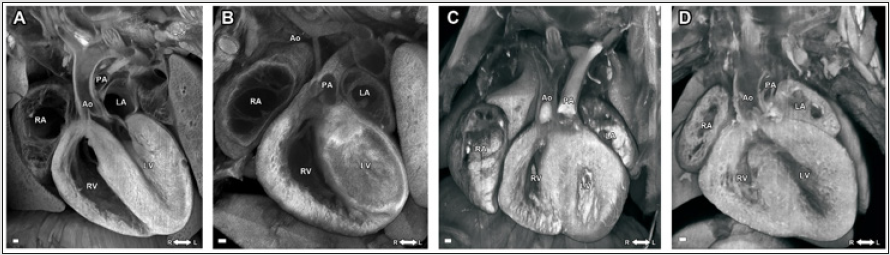

Histopathological imaging with episcopic confocal microscopy (ECM) is the ultimate gold standard for validating the diagnosis of birth defects in mouse embryos and neonatal pups. With ECM imaging 12, 17, 19, the paraffin embedded specimen is sectioned using a sliding microtome with a fixed photoposition, and the block face is serially imaged after each cut using a laser scanning confocal macroscope mounted over the microtome (Figure 3). In this manner, the 2D serial image stack collected of the specimen is in registration, allowing rapid 3D reconstructions to be generated and it is possible to digitally re-slice the serial 2D image stack in any imaging plane. In this manner, it is possible to make a complete assessment of any structural cardiac anomaly, regardless of the embedding plane of the specimen. This ECM histopathology has all the conveniences of micro-CT or micro-MRI data, but with the much higher resolution (5 μm) achieved by histology.

On the other hand, micro-CT and micro-MRI allow simultaneous whole-body imaging for multiple mouse embryos or neonatal mouse pups, whereas the ECM can only section and image much smaller sample size, only 1 organ/tissue from 1 single embryo at a time. Figure 3 shows single imaging plane out of the 3D multiplanar ECM imaging stacks of embryonic mouse hearts from a normal wild-type embryo (Figure 3A), a mutant embryonic heart with hypoplastic left heart syndrome (HLHS) (Figure 3B), a mutant embryonic heart with double outlet right ventricle (DORV) (Figure 3C), and a mutant embryonic heart with atrioventricular septal defect (AVSD) (Figure 3D).

Figure 3: ECM images of (A) a normal wild-type; (B) mutant embryonic heart with hypoplastic left heart syndrome (HLHS); (C) mutant embryonic heart with double outlet right ventricle (DORV) (D) mutant embryonic heart with atrioventricular septal defect (AVSD). LV: left ventricle; RV: right ventricle; LA: left atrium; RA: right atrium; Ao: aorta; PA: pulmonary artery.